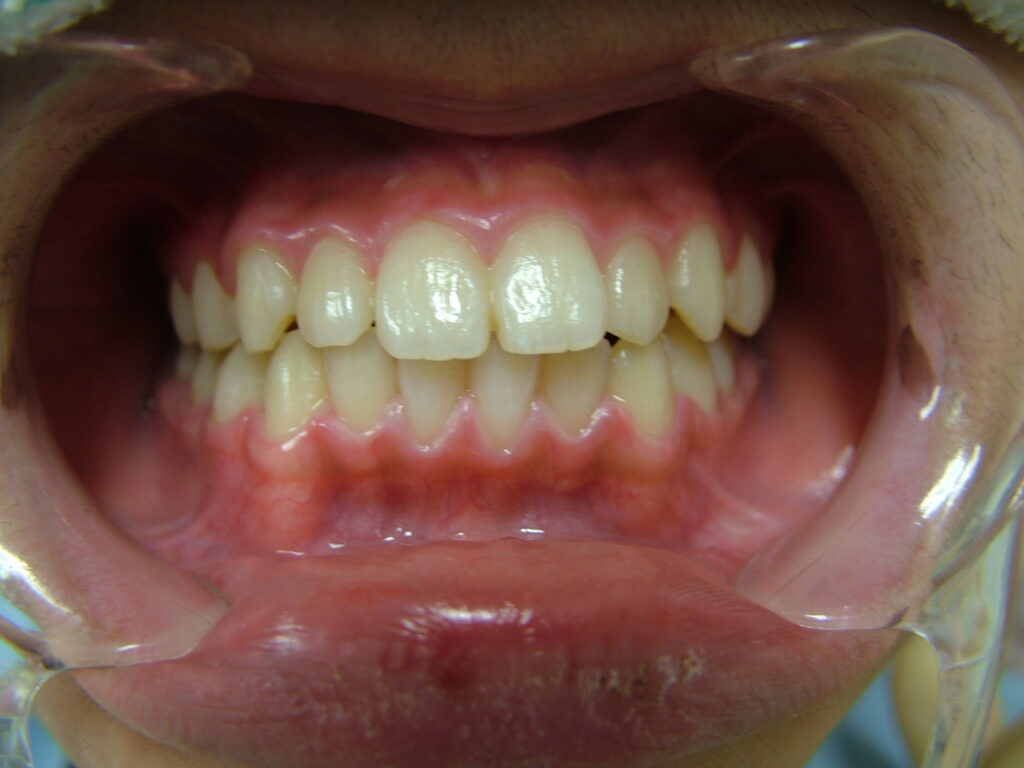

治療前

- 初診:2014年、8歳男児、

- 主訴:上の歯の隙間と歯の傾きが気になる。

- 診断:1級咬合、左偏位、下永久歯(犬歯)萌出スペース不足